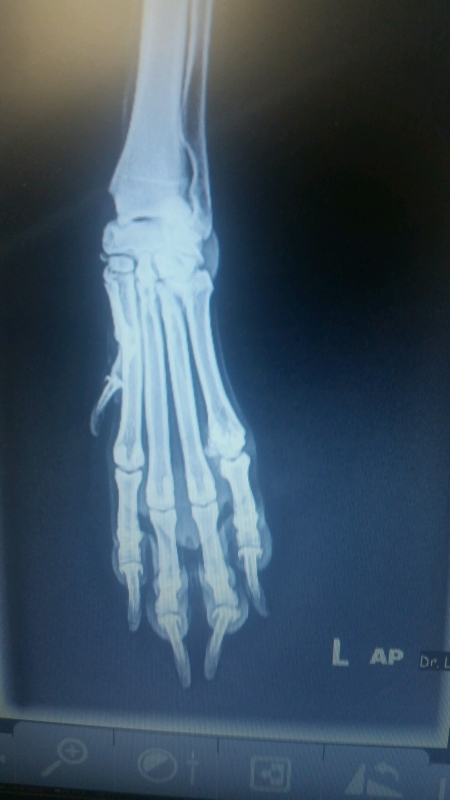

Calli has no break. But signs of arthritis. Poor baby.

So she’s off walk duty for a while. Which doesn’t make her happy.